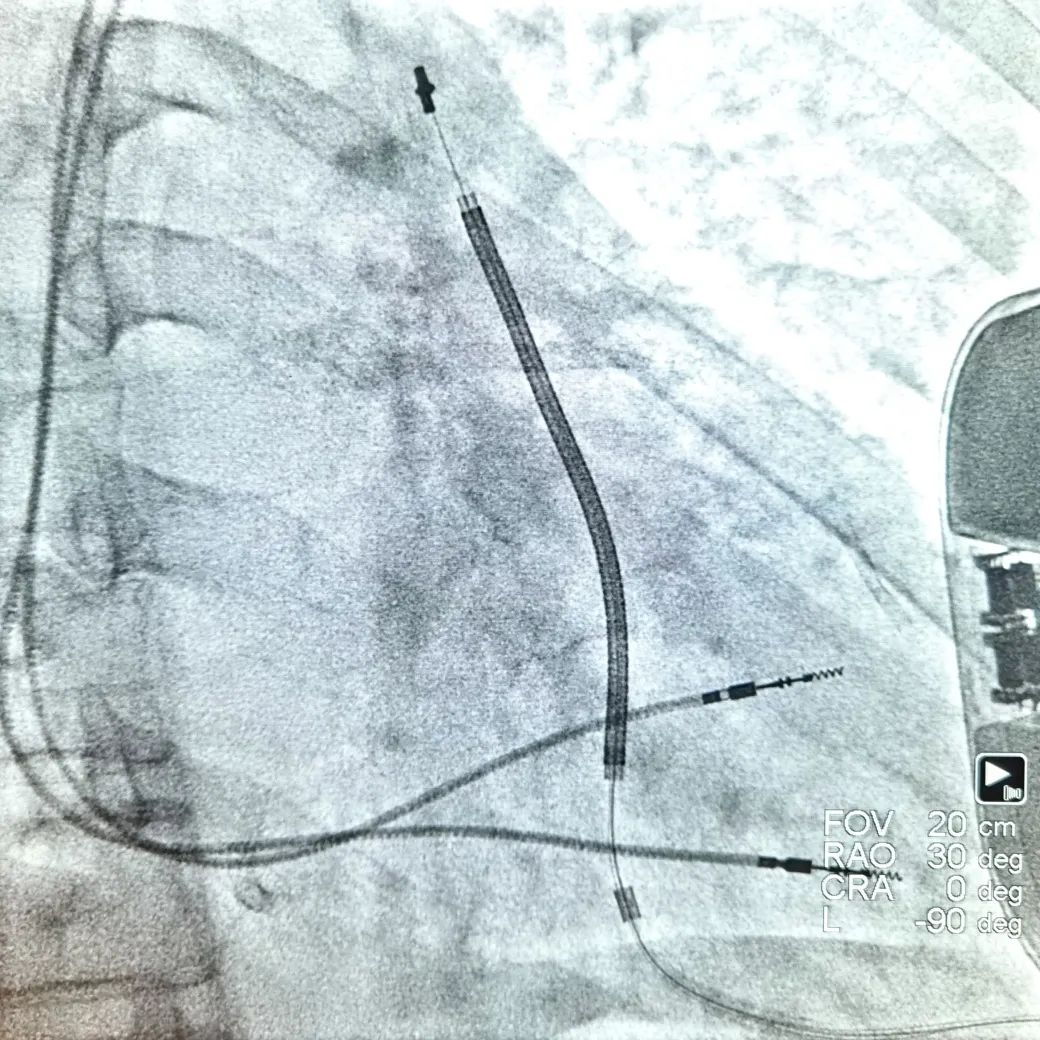

该手术需要注意S-ICD的“全皮下”特性和CCM的两根导线摆放位置,传统ICD感知的是腔内局部的电活动,而S-ICD所感知的是类似于体表心电图。而CCM是在感知到QRS波的绝对不应期发挥作用,二者工作模式有交互,尤其是S-ICD会感知CCM工作状态下对QRS波的改变,而增加“噪音N”的比例记录。姚娟教授凭借丰富的植入经验,术中首先植入S-ICD,植入后抓取模板,优化向量,随后暂时关闭S-ICD抗心动过速功能。再植入CCM,两根心室导线于右室间隔中低位,两根导线间距大于2cm,两根导线感知阈值均大于10mv,起搏阈值均为0.6v,阻抗分别为560Ω和700Ω,表明导线植入在健康的心肌上。测试完连接CCM植入,调整参数在保证正常发送比率的同时减轻对S-ICD的干扰识别,开启S-ICD功能,经过双机器同步程控测试,消除了S-ICD对CCM的工作状态识别为“噪音N”的干扰,二者均正常发挥功能。CCM联合S-ICD一站式植入顺利完成,手术全程用时2小时。